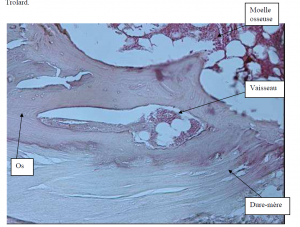

Photo INSERTIONS DE LA DURE-MERE SUR LE RACHIS Une anatomie redécouverte 32